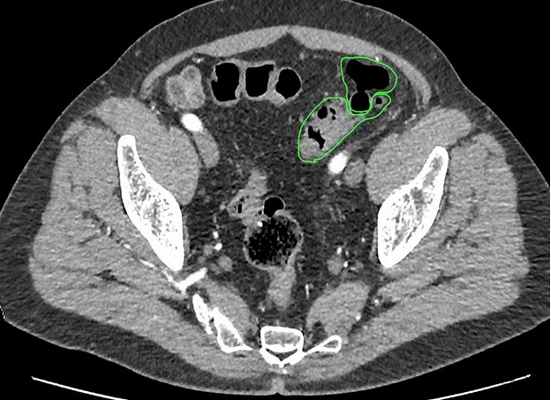

Не менее важными методами являются ультразвуковая диагностика и компьютерная томография. Благодаря своей малоинвазивности, простоте выполнения, ультразвуковая диагностика очень актуальна на этапе первичного обследования. Она позволяет увидеть наличие дивертикулов, выявить косвенные признаки их воспаления, такие как инфильтрат, абсцесс или предположить генерализованную форму – перитонит.

Для уточнения данных, полученных при ультразвуковом исследовании, при возникновении сомнений и для уточнения диагноза выполняется спиральная компьютерная томография. Виртуальная компьютерная томография позволяет воссоздать трехмерное изображение толстой кишки, включая пораженные участки. С помощью этой методики можно точно определить границы инфильтрата или абсцесса, другие органы, вовлеченные в воспалительный процесс.

Рисунок 5. Виртуальная колоноскопия. Устье дивертикула